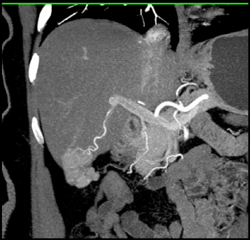

Focal Nodular Hyperplasia (FNH)